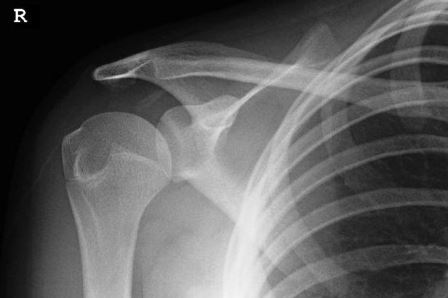

Các bác sĩ chẩn đoán, Lauren mắc một triệu chứng hiếm gặp có tên là Ehlers-Danlos, điều này có nghĩa hệ thống gân cốt và sụn của Lauren quá yếu, do đó không thể cố định vị trí của khớp xương khi bị một tác động nhẹ.

Lauren Harry đã phải chịu những cơn đau đầu tiên ở chân khi cô mới 11 tuổi, nhưng hiện tượng đau chân khi đó được chẩn đoán là do sự phát triển của cơ thể. Đến năm 15 tuổi, Lauren đã bị té nạng và dẫn đến việc khớp vai bị chấn thương. Kể từ đó, một số khớp xương trong cơ thể bao gồm đầu gối và ngón tay thường xuyên bị trật khớp.